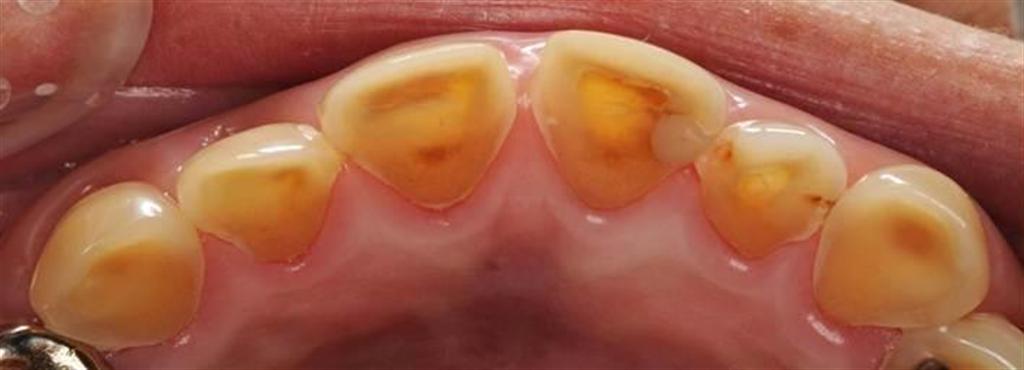

黒酢の原液を飲み続けて、象牙質が露出した状態になった酸蝕歯(東京医科歯科大提供)